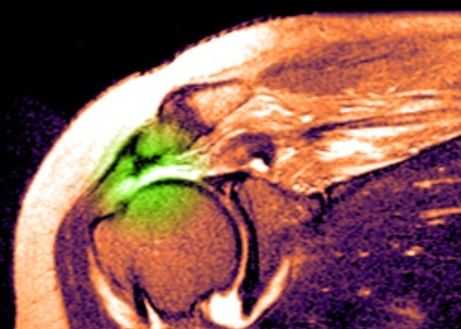

МРТ плечевого сустава. Т2-взвешенная корональная МРТ. Разрыв вращательной манжеты. Цветовая обработка изображения.

При МРТ плечевого сустава косвенным признаком разрыва вращательной манжеты служит высокий сигнал на Т2-взвешенных от поверхности сустава до субакромиальной (субдельтовидной) сумки. Частичные разрывы чаще всего по передней поверхности сухожилия м.supraspinatus, реже примыкая к большой бугристости или сухожилия м. infraspinatus.